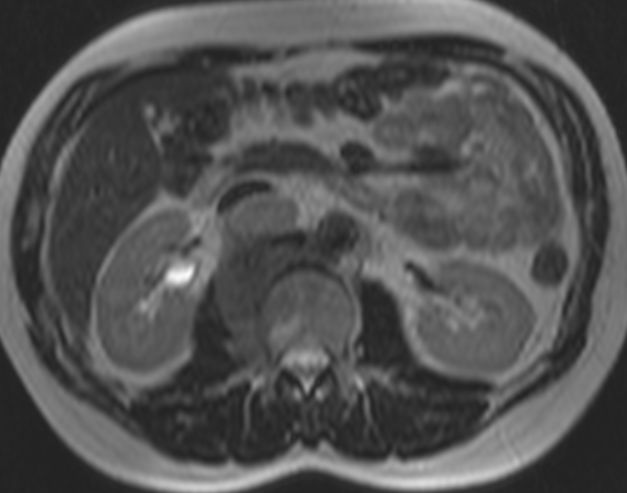

Rezidiv 1 Jahr nach follikulärem Lymphom

MRT